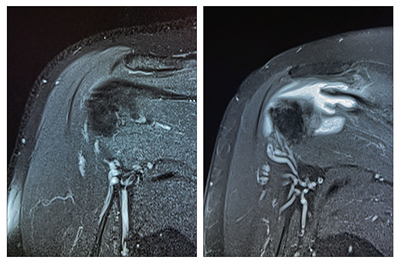

초음파검사에서는 회전근개 힘줄 손상이 자주 관찰된다. 회전근개는 어깨를 둘러싼 4개의 근육으로 구성되어 있으며, 이중 극상근과 견갑하근 힘줄손상이 골퍼들에게 가장 흔하다. 극상근은 골프 스윙 중 견봉이라는 뼈와 충돌하기 쉽고, 이 충돌은 주로 어드레스와 백스윙 시 발생한다.

반면, 팔로우 스루 동작에서는 우세하지 않은 어깨에서 오버헤드 모션으로 인한 충돌이 일어난다. 빠른 스윙과 반복적인 동작으로 인해 작은 파열이 발생하고, 이것이 극상근의 전층 파열로 이어질 수 있다. 어깨 앞쪽의 견갑하근 힘줄 손상도 흔한데, 이는 골프 스윙 중 내회전하는 동작으로 인해 발생한다.